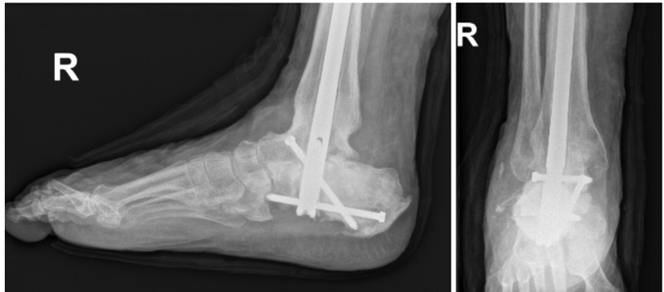

After 68 days, stage two was performed involving removal of external fixator, removal of drug delivery devices, and insertion of definitive tibiotalocalcaneal arthrodesis nail. Routine monthly radiographs and repeat inflammatory markers were followed. At the time of the second stage, inflammatory markers improved significantly with ESR reduced to 32 mm/hr and CRP to 6 mg/dL. Radiographic evidence of bony fusion across the ankle and subtalar joints was observed 61 days following stage two (Figure 5). The patient progressed to partial weight bearing at 26 days post-operatively. At final follow-up, all surgical wounds were fully healed, with no recurrent signs of infection or hardware complications.

Figure 5 Foot and ankle radiographs demonstrating tibiotalocalcaneal fusion with use of an intramedullary nail at 12 month follow-up.